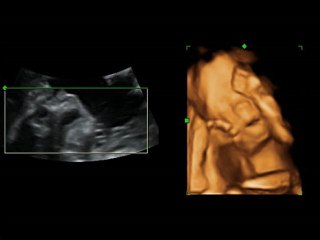

Anne karnındaki bir bebek, anne ve babasının şarkı söylemesi üzerine alkış tutmaya başladı